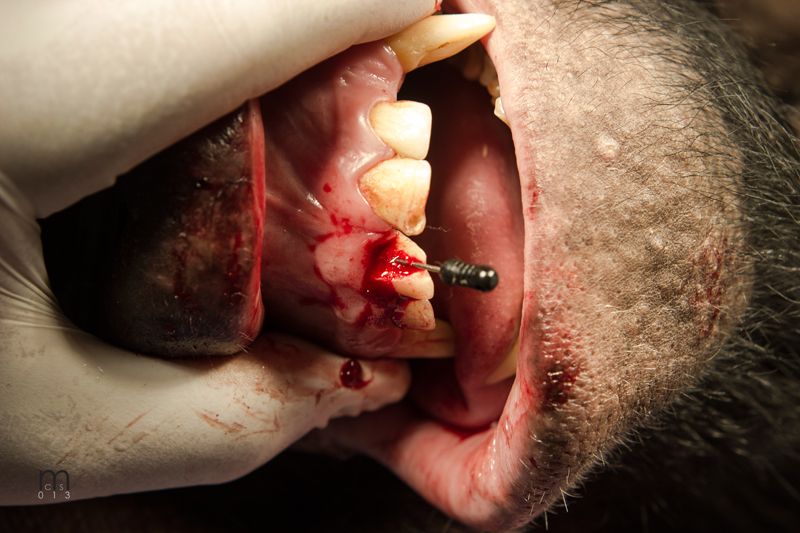

Fistula explored

Fistula exposed

Fistula being repaired

Fistula exposed, tensionless flap